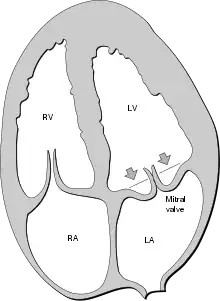

Echocardiography is the most useful method of diagnosing a prolapsed mitral valve. Two- and three-dimensional echocardiography is particularly valuable as they allow visualization of the mitral leaflets relative to the mitral annulus. This allows measurement of the leaflet thickness and their displacement relative to the annulus. Thickening of the mitral leaflets >5 mm and leaflet displacement >2 mm above the annular plane in parasternal long-axis view indicates classic mitral valve prolapse.[35]

Prolapsed mitral valves are classified into several subtypes, based on leaflet thickness, type of connection to the mitral annulus, and concavity. Subtypes can be described as classic, nonclassic, symmetric, asymmetric, flail, or non-flail.[35]

Classic versus nonclassic

Prolapse occurs when the mitral valve leaflets are displaced more than 2 mm above the mitral annulus high points. The condition can be further divided into classic and nonclassic subtypes based on the thickness of the mitral valve leaflets: up to 5 mm is considered nonclassic, while anything beyond 5 mm is considered classic MVP.[35]